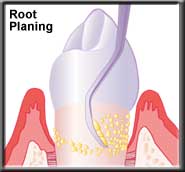

Root planing smoothes the root surface |